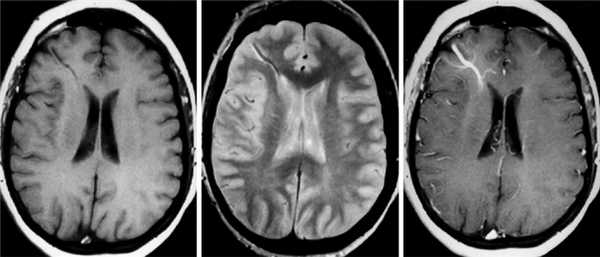

При КТ без контрастного усиления SP имеет большую плотность по отношению к окружающим структурам мозга. Также КТ позволяет выявить наличие дефекта костей свода черепа. При КТ с внутривенным контрастированием SP имеет такую же плотность, как другие венозные структуры, исключением являются случаи тромбированного SP [26].

МРТ дает информацию о содержимом синуса на основании характеристик сигнала и взаимосвязи патологического образования и подлежащего синуса [39]. Данные МРТ больного Д. указывали на наличие патологического образования, характеризующегося сигналом со смешанной интенсивностью. Это было обусловлено турбулентным кровотоком. Для определения взаимосвязи образования и синусов твердой мозговой оболочки используют магниторезонансную или компьютерную венографию [7].

В случае пациента Д. проведения МРТ и спиральной компьютерной ангиографии головного мозга явилось достаточным для установления диагноза. В случае пациента М. данные спиральной КТ неубедительно указывали на отсутствие артериовенозного шунтирования.